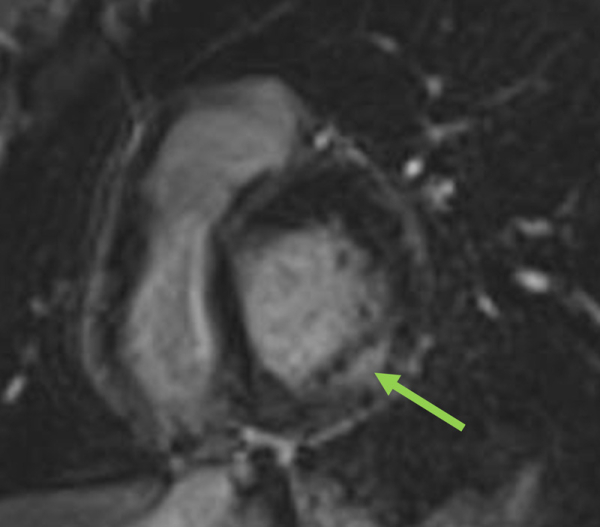

- IRM cardiaque : une hypertrophie biventriculaire, la présence de fibrose myocardique mésomyocardique inféro-latérale basale (Figure 3) mais plus précocement encore on peut simplement observer un abaissement du signal T1 sur les cartographies myocardiques < 950 ms (et parfois une élévation du T2). À noter que, chez la femme tout particulièrement, la fibrose myocardique (RT) peut précéder l’hypertrophie VG dans 40 à 50 % des cas, d’où l’importance de sa réalisation avec injection et des cartographies de mapping T1 (et T2) systématiques. L’aorte initiale peut être dilatée du fait de la maladie ;

Figure 3 : présence de fibrose myocardique mésomyocardique inféro-latérale typiquement observée en IRM cardiaque (10 min après injection de Gadolinium) dans la maladie de Fabry,

ici chez une femme Fabry avec HVG mesurée à seulement 11-12 mm